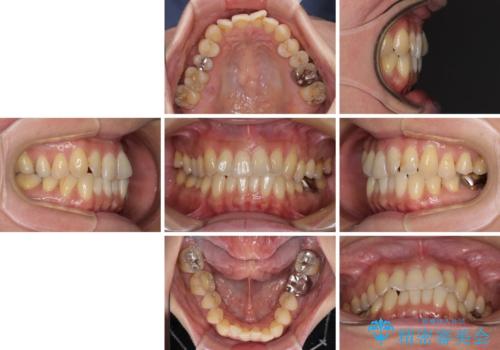

- 前歯のクロスバイトが気になり、インビザラインによる矯正治療を希望して来院された患者様です。

上顎側切歯(上の真ん中から2番目の歯)が舌側転位している場合、インビザラインでは仕上げきれないことが多く、更には無理して動かそうとすると歯髄壊死を起こすリスクが高いと言われています。

インビザラインで歯列を移動する前に、上顎前歯をワイヤー矯正で整え、その後上下歯列をインビザラインにて矯正治療を行うこととしました。